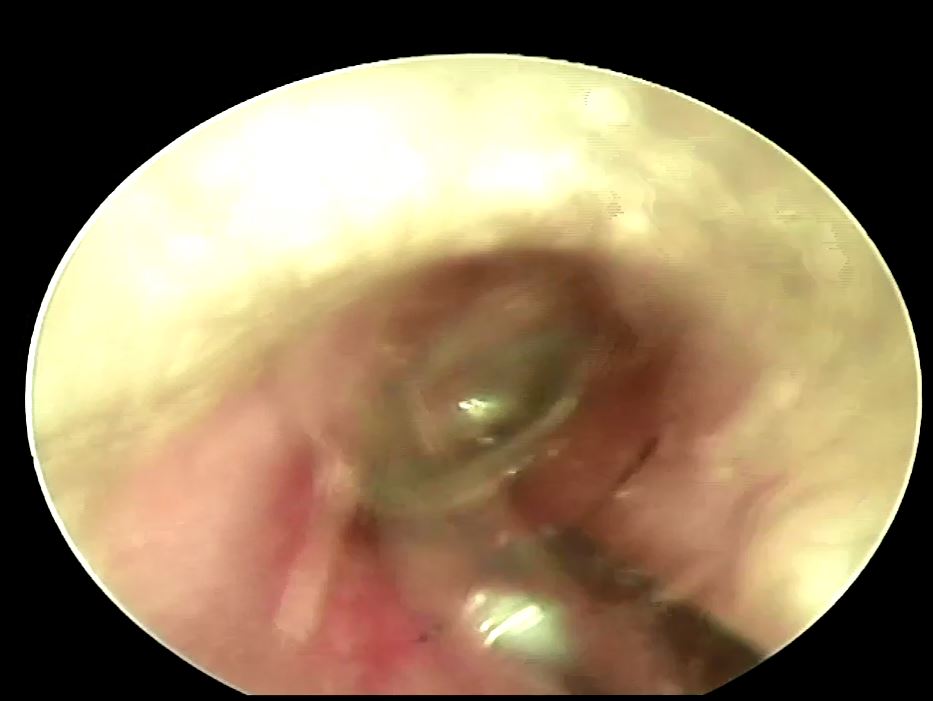

耳朵內的異物最難取出的是耳垢或是蟲子嗎? 答案都不是,最拿取出的其實是最微不足道的"頭髮"!! 而且是卡在最深處的頭髮,最近遇到一位病人一直覺得耳朵內有時會有怪聲合併輕微的耳悶,後來仔細一看原來是在耳膜上卡了一根頭髮,在內視鏡輔助下花了一點時間終於幫病人解決問題,有耳悶情形的話提醒大家可以到耳鼻喉科檢查一下喔!!